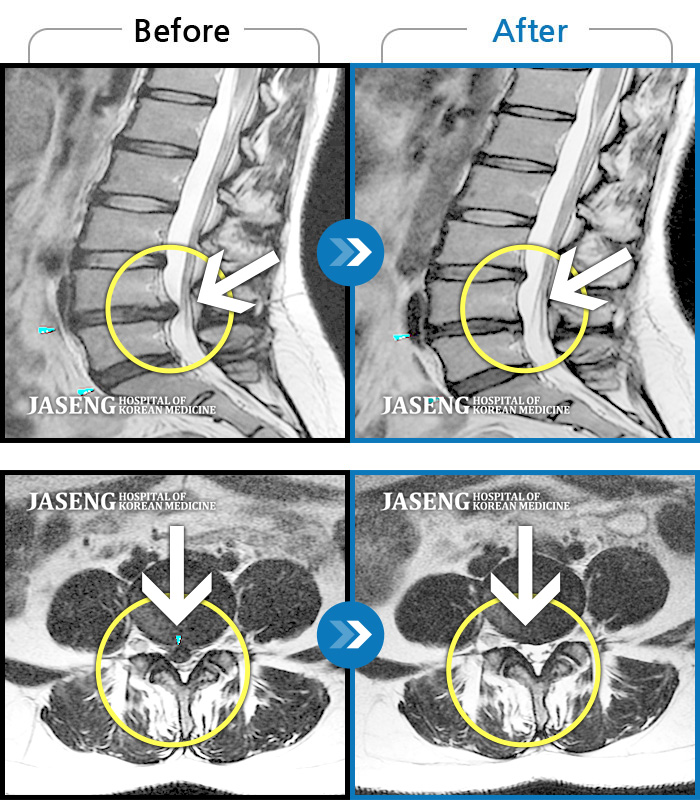

MRI 치료사례

허리 통증 및 우측 엉치 다리에 통증